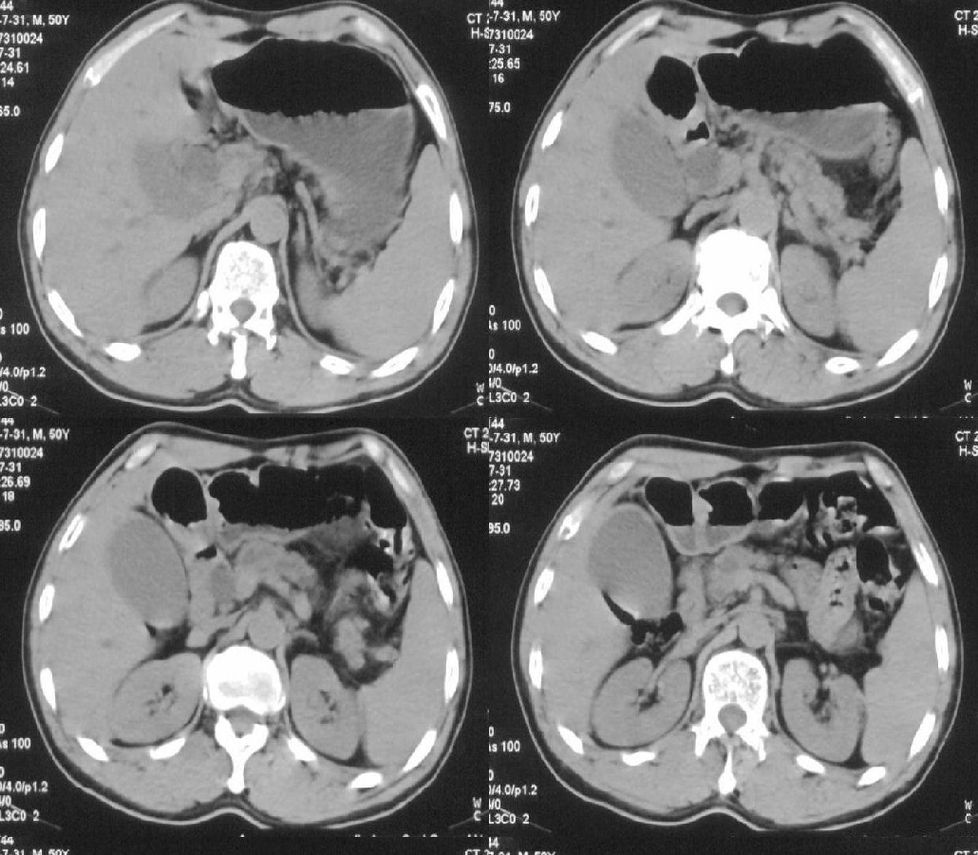

标题: CT21384:男性,50岁。发现无痛性黄疸十余天,B朝提示肝胆管 [打印本页]

标题: CT21384:男性,50岁。发现无痛性黄疸十余天,B朝提示肝胆管

1.考虑:壶腹占位病变(癌?)。

2.胆系低位梗阻:肝内外胆管扩张,胆囊增大,胰管扩张。

胰头癌伴低位胆道梗阻。

胆系低位梗阻(肝内外胆管扩张,胆囊增大,胰管扩张);考虑胰头癌或壶腹癌所致。

胆总管突然中断,壁增厚且强化,考虑胆总管癌可能性大伴胆系梗阻,胆囊炎

胰头强化欠均匀,胆胰管扩张。考虑胰头癌可能性大。

胆系低位梗阻(肝内外胆管扩张,胆囊增大,胰管扩张,钩突似有占位);考虑胰头癌